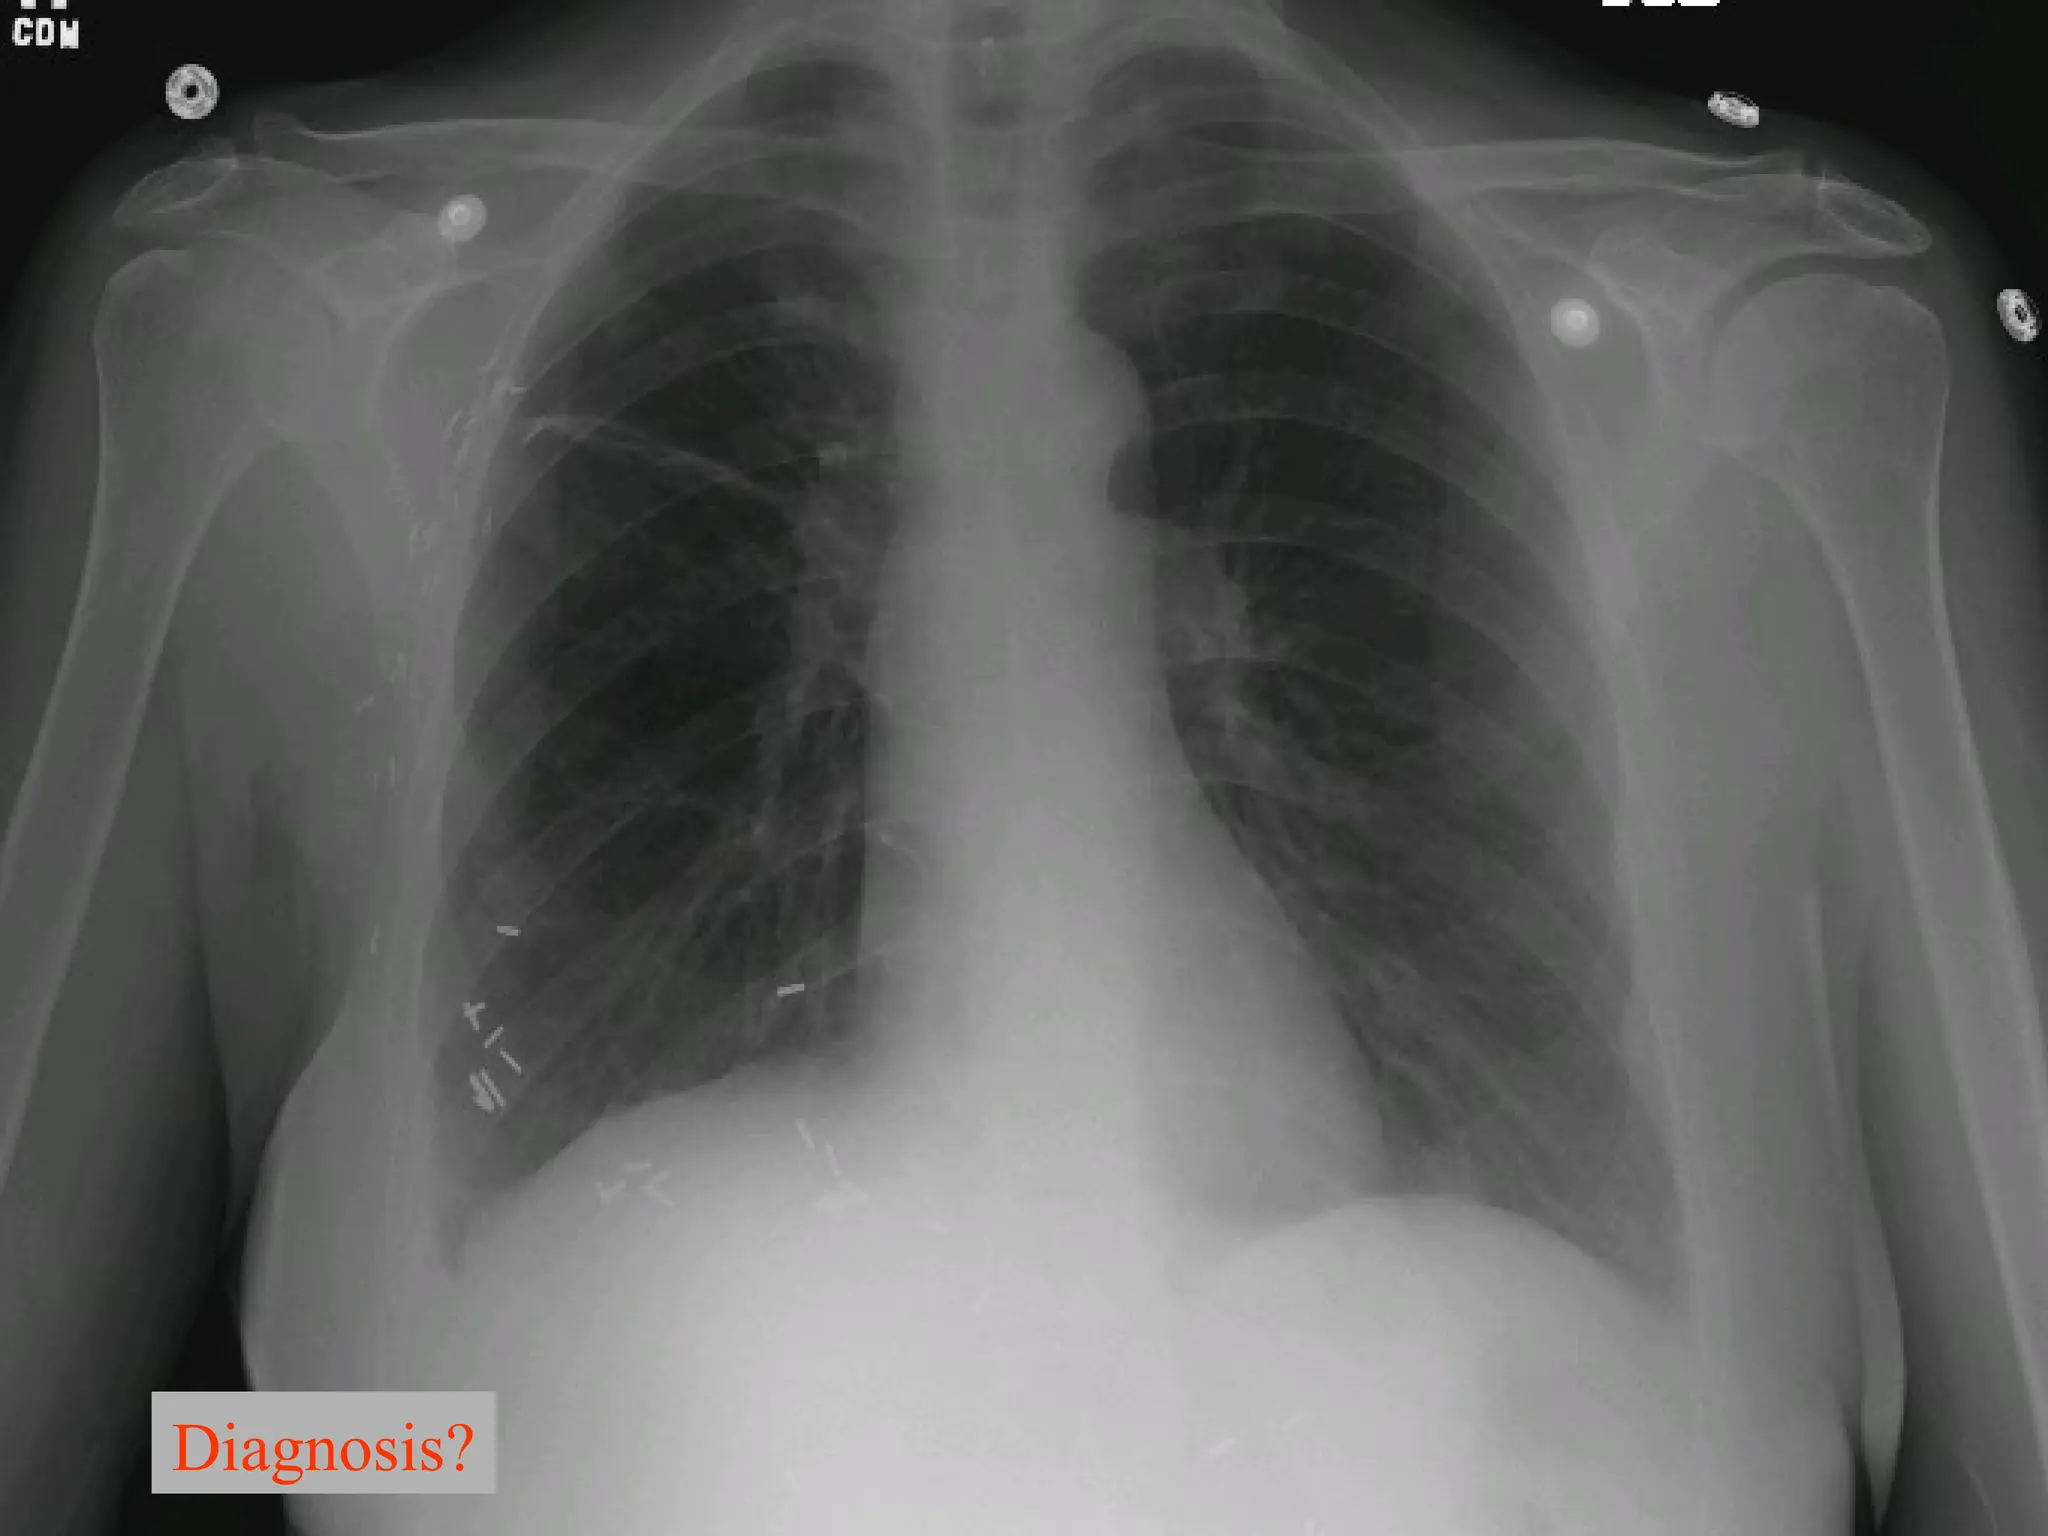

Diagnosis?

A broken central venous catheter has

migrated into the right lower

lobe pulmonary artery